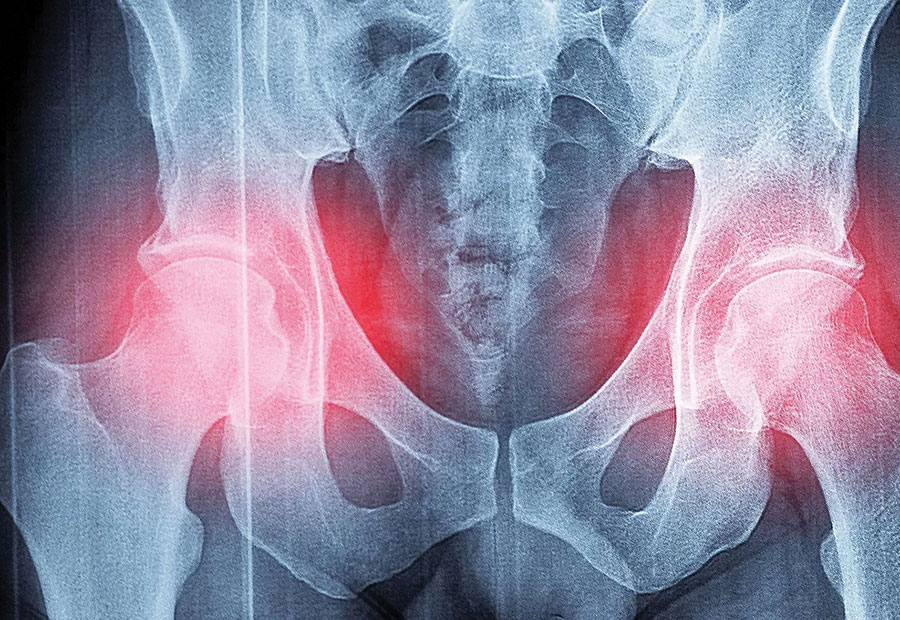

L’ostéoporose se caractérise par une diminution accélérée de la masse osseuse et une détérioration de l’architecture osseuse : l’os devient frêle et cassant, sujet aux déformations. Une chute banale peut alors entraîner une fracture, bien souvent du poignet, des vertèbres ou du col du fémur.